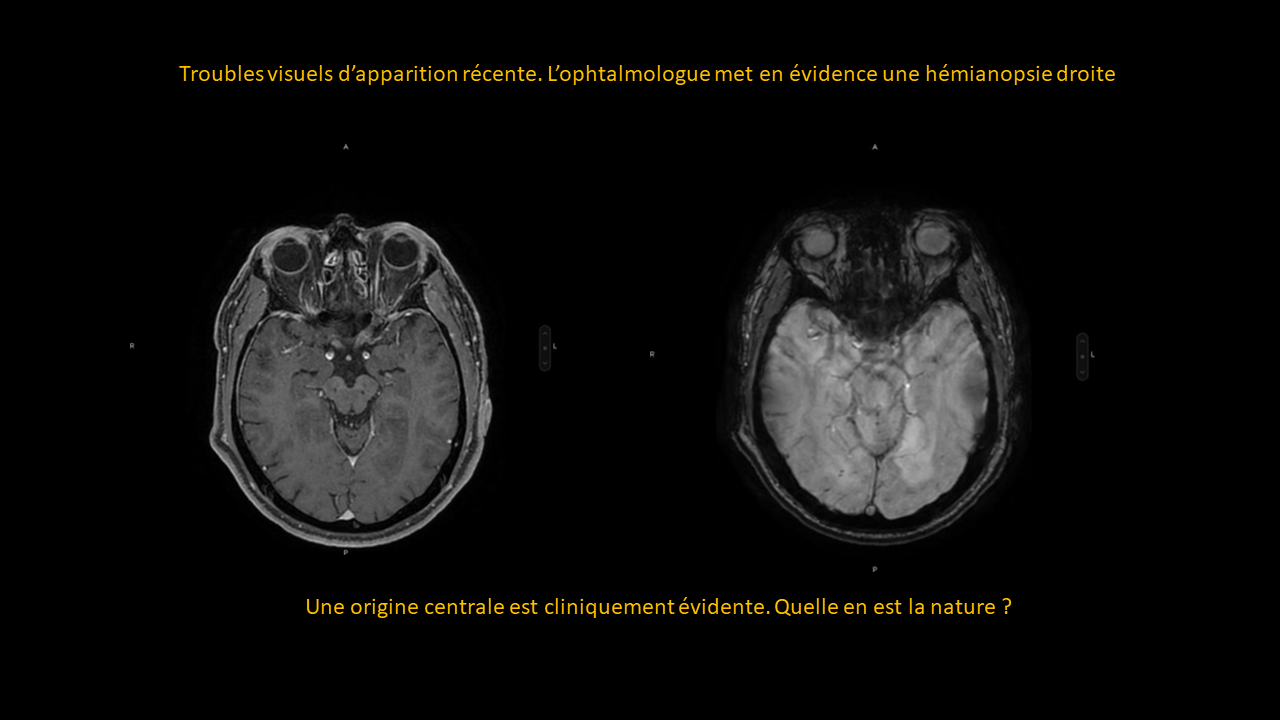

Formation continue sous forme de vignettes ( Quiz )